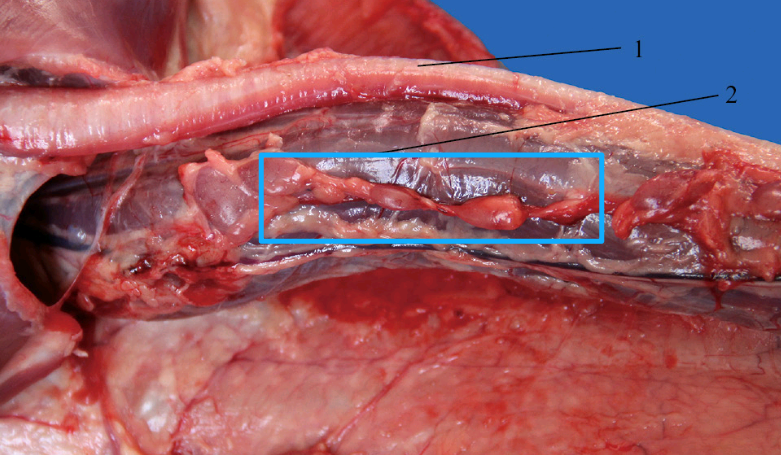

圈出部位为鸭子的淋巴结(图源:参考资料[3])

大家看到一个个圆鼓鼓的,其实是胸腺。胸腺是T淋巴细胞分化、发育和成熟的场所,是机体最重要的中枢免疫器官之一[3]。它负责“训练”免疫细胞,而不是像淋巴结那样直接过滤和清除病原体。因此,胸腺与淋巴结相比,更“干净”。

圈出部位为鸭子的胸腺(图源:参考资料[3])